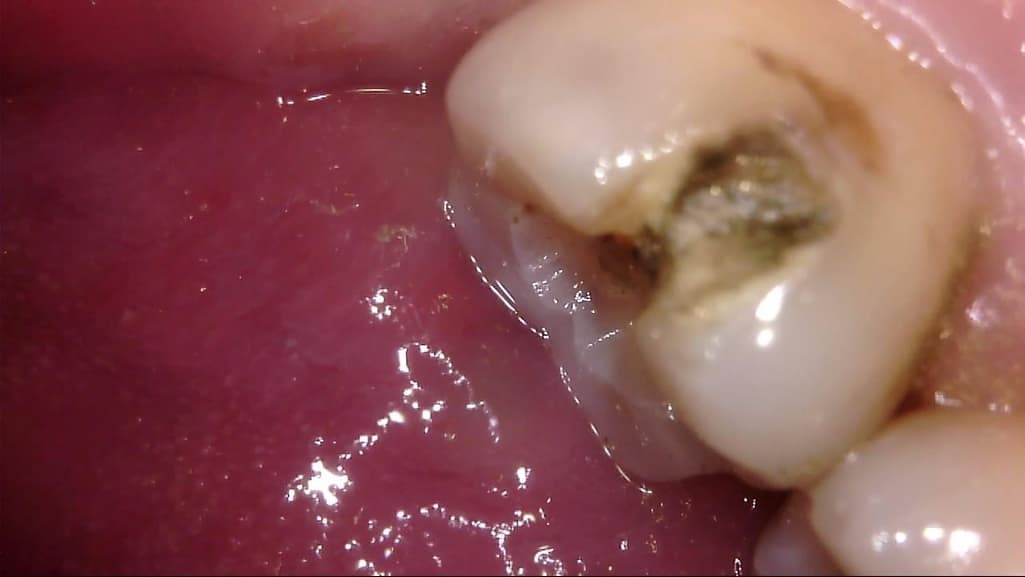

이차 우식이 상당히 깊게 발생하였는데, 치료 과정에서는 아래 사진과 같이 선생님께서 아래와 같이 일부 갈색 부분을 남긴 채 치아 삭제를 마치고 보철을 진행해 주셨습니다.

선생님께서는 "해당 부분은 착색 부위로, 이대로 덮어도 무방하다"라고 말씀 주셨고, 저 역시 더 이상 파고들어가면 신경치료가 예상되어 최선의 치료를 해 주셨다고 생각합니다.

다만 1) 해당 부위가 우식이 아닌 '착색'이 맞는지, 2) 해당 상태에서 보철물 안에서 추가 우식이 빠르게 진행될 가능성이 있는지, 3) 차라리 신경치료를 감수하고서라도 갈색 부분을 전부 없애는게 나았을지 불안감이 있는데, 관련하여 고견을 여쭙고 싶습니다.

사진에 보이는건 일단 착색과 2차 충치가 섞여 잇는거 같습니다. 충치를 제거하는 저스피드 기구로 제거를 해보기너 눌러 봐서 단단하면 충치가 아닙니다.

사진으로 보이는 부분은 충치에 어느정도 영향을 받은 부위는 맞습니다. 하지만 감염이 되어 있는것으로 보이지는 않습니다.

착색은 아니고 이환 상아질 남긴 것 같습니다 감염 상아질은 깔끔하게 다 제거 됐습니다